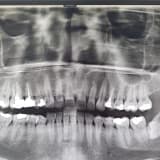

Diş apsesi, dişin pulpa dokusunun veya dişi çevreleyen yumuşak doku olan periodonsiyumun patojen bakteriler tarafından istila edilmesi sonucu gelişen bir enfeksiyondur. Bu patojenler, diş kök yüzeyine erişerek ilgili bölgede iltihap oluşmasına neden olur. Diş sağlığını ciddi şekilde tehdit eden bu durum, profesyonel bir müdahale gerektiren klinik bir tablodur.

Diş enfeksiyonlarını önlemek ve mevcut durumu iyileştirmek için izlenmesi gereken ilk adım, uzman bir hekim tarafından yapılacak klinik muayene ile enfeksiyonun ciddiyetinin belirlenmesidir. Tedavi planı, enfeksiyonun durumuna göre şu aşamaları içerir:

- Kanal Tedavisi: Etken olan dişin kurtarılması mümkünse, öncelikle kök kanal tedavisi uygulanır.

- Diş Çekimi: Kanal tedavisinin mümkün olmadığı durumlarda dişin çekilmesi zorunluluk haline gelir.

Sonuç olarak, toplumda yaygın bir soru olan "Apseli diş çekilir mi?" sorusunun cevabı; hekim tarafından uygun görüldüğü takdirde evet, apseli dişlerin çekimi yapılabilir. Tedavi sürecinin bir diğer önemli parçası olan antibiyotik kullanımı ise vakaya göre ayrıca değerlendirilmesi gereken bir konudur.